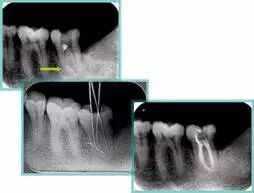

6. 术后 X 线片

术后 X 线片用来评定根管充填 长度、致密度(管壁清晰、侧枝)等指标。

牙胶尖什么颜色​牙齿“晓”“技”|最全根管治疗的标准步骤,以及细节把握_https://www.jmylbn.com_新闻资讯_第16张

左图为根管充填术后 X 线片。图中可见,根管充填较好。右下图有白色小点,为侧方加压导致糊剂挤出所致,表明根管充填比较致密。

致密、恰到好处的充填可去除干净根管里感染灶,机体逐渐恢复。

牙胶尖什么颜色​牙齿“晓”“技”|最全根管治疗的标准步骤,以及细节把握_https://www.jmylbn.com_新闻资讯_第17张

多根牙时候需进行偏移投照,正位投照无法说明具体哪根牙根管充填效果。        二、根管预备及充填要求